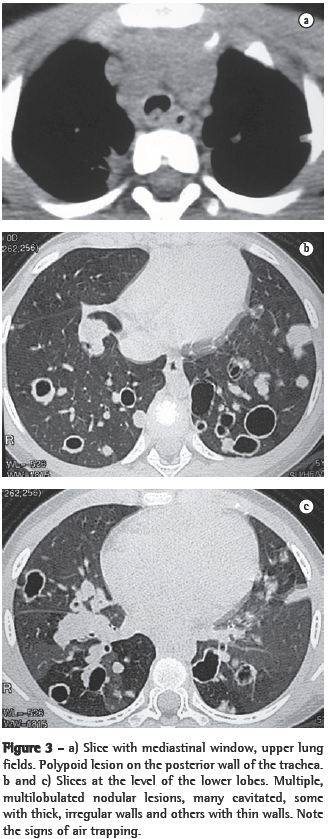

In all eight cases, the CT scans revealed polypoid formations in the trachea. In one case, injury to one of the main bronchi was identified. Seven patients presented involvement of the pulmonary parenchyma. In all eight cases, there were cavitated polypoid lesions, with irregular internal borders and walls of various thicknesses, multilobulated in six cases and presenting confluence of the lesions in five (Figures 1 through 5). Solid nodules were seen in six patients. An air-fluid level was observed in only one patient. The lesions were predominantly in the lung bases in three patients and in the middle thirds in two, whereas they were evenly distributed in two. In one patient, the lesions were accompanied by a mass, and, in another patient, they were accompanied by consolidation. In the latter case (Figure 5), there was malignant degeneration in multiple lesions. Signs of air trapping were also observed in one case. There were no identified instances of lymph node enlargement or pleural effusion.

Chest X-rays are inferior to CT scans of the chest, especially those performed using spiral CT (volumetric acquisition), in the initial phases of pulmonary dissemination, due to the fact that CT better characterizes and allows better visualization of nodular tracheobronchial vegetation, Tomographic findings include focal or diffuse airway narrowing caused by the nodules. The nodules form on the mucosal surface, and their invasion into the lumen is best evaluated using CT.(3) These alterations are easily correlated with the disease when there is a clinical history of papillomatosis.(4) Other findings related to airway obstruction and accompanying infections are atelectasis, consolidations, air trapping and bronchiectasis.(2-4) In our sample, polypoid formations in the trachea were observed on all of the CT scans Seven patients presented involvement of the pulmonary parenchyma, characterized by cavitated polypoid lesions with irregular internal borders and walls of various thicknesses, with a multilobulated aspect and a tendency toward confluence. Solid nodules were seen in six patients. None of the patients presented lymph node enlargement or pleural effusion.